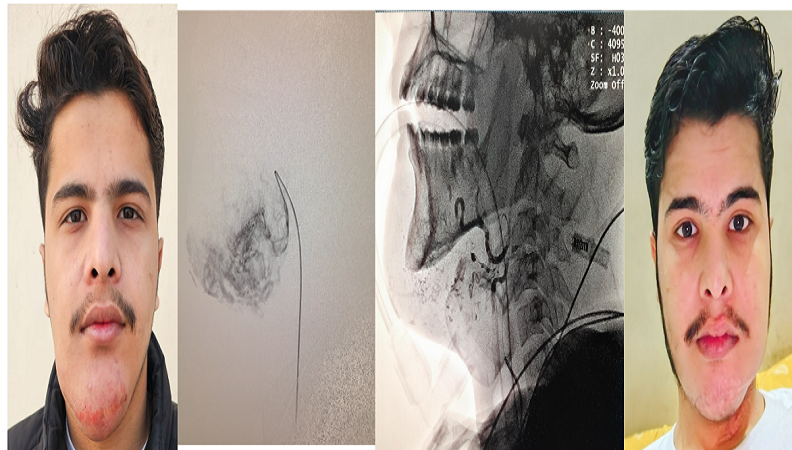

Facial VascularVenous Vascular Malformations Embolization

VENOUS VASCULAR MALFORMATION (VVM)

This is the most common type. These can often be treated by injecting a substance that is toxic to the veins. This irritates them, scars them, and causes them to get smaller. This procedure is also known as ‘sclerotherapy’. The substance we use to do this is called Bleomycin. This is a drug which is used in much higher concentrations to treat certain cancers. We use very low doses of it. This is performed as a day-case procedure, using sedation. We use very small needles to puncture the venous malformation, using x-rays or ultrasound to help identify it. We then inject small amounts of bleomycin into as many areas of the venous malformation as we can. You can usually go home an hour or so after the procedure. This treatment is often repeated several times, spaced out over a few weeks each, in order to treat as much of the abnormal veins as possible. Occasionally the venous malformation can swell and even temporarily get slightly bigger as a result of treatment. This usually resolves over time.  Sometimes the treatment causes the venous malformation to completely disappear, but usually they just get smaller. Treatment usually helps to reduce swelling episodes and related pain. Sometimes they will vanish but leave a hard “scar” of tissue under the skin, where they used to be. It varies from person to person. What we often recommend is that you undergo a few sessions of sclerotherapy. After that we will reassess things, and may recommend more treatment if it is having good effect.

ARTERIOVENOUS MALFORMATION (AVM)

This type is less common, and treatment is more complicated. We usually see these patients along with a plastic surgeon with a special interest in treating these lesions. We can often treat them together in a combined approach. This means a multi-stage procedure, performed under general anaesthetic. The first step is treating the AVM from inside the blood vessels. By inserting small tubes/catheters into the blood vessels at the groin, we can then navigate these to the blood vessels affected. We can than inject a special substance called ‘Onyx’ into the blood vessels feeding the AVM. This is a special type of liquid that then hardens and closes off the blood vessels. This hard substance remains under the skin or deep in the soft-tissues. That is why the next step, which happens a few days/weeks later, involves the plastic surgeon removing the AVM. Again, this type of treatment is not as common as the other type, and we will discuss this in detail with you if we are recommending it.